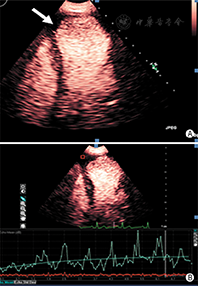

清晰地显示左心室心内膜边界是准确评价左心室功能的关键。国外临床试验表明,常规超声心动图检查时70%~90%的心血管超声图像不佳(图像质量不佳定义:在任何一个心尖长轴标准切面有2个或2个以上的连续心肌节段的心内膜结构不能清晰显示),通过使用造影剂后可明显提高诊断图像的解剖结构分辨率[15,16,17](图2)。在心脏解剖结构和功能异常状态判断存在疑问时也可考虑使用超声造影剂。当静息状态不能满意获得常规超声心动图图像时,造影剂用于左心室心腔造影尤其有帮助,这常见于肥胖、有肺部疾患、病情危重或接受呼吸机护理的患者。如果在这些患者中优化了换能器频率、扇扫宽度、图像深度和聚焦位置,心脏超声图像质量仍不理想,应当考虑使用造影剂。负荷超声心动图检查达峰值负荷时图像质量不理想的情况常较明显,此时使用造影剂将明显提高图像质量、增强判断信心和诊断准确性。此外使用造影剂将明显提高有经验和无经验医师解释图像的重复性和准确性[18,19,20]。

LVEF的准确测量对心血管疾病患者的治疗极为重要,对预测心肌梗死后及血运重建后充血性心力衰竭患者的不良事件具有重要价值。超声心动图是目前唯一能够床旁提供实时动态连续心脏解剖结构和功能动态评估的可视化医学影像技术方法,与其他影像技术相比,具有无电离辐射、容易获取、便携和成本相对较低的优势。已有研究发现常规的非增强超声心动图测量的LVEF与公认的金标准相比有显著差异,观察者间一致性低,因此严重影响了常规超声心动图心功能测量的实用性和可靠性。最近的一些研究表明,造影超声心动图测量左心室容积和LVEF与核素显像、MRI、CT有着良好的相关性,并且提高了观察者间的一致性及医师诊断信心[21,22,23](图3)。